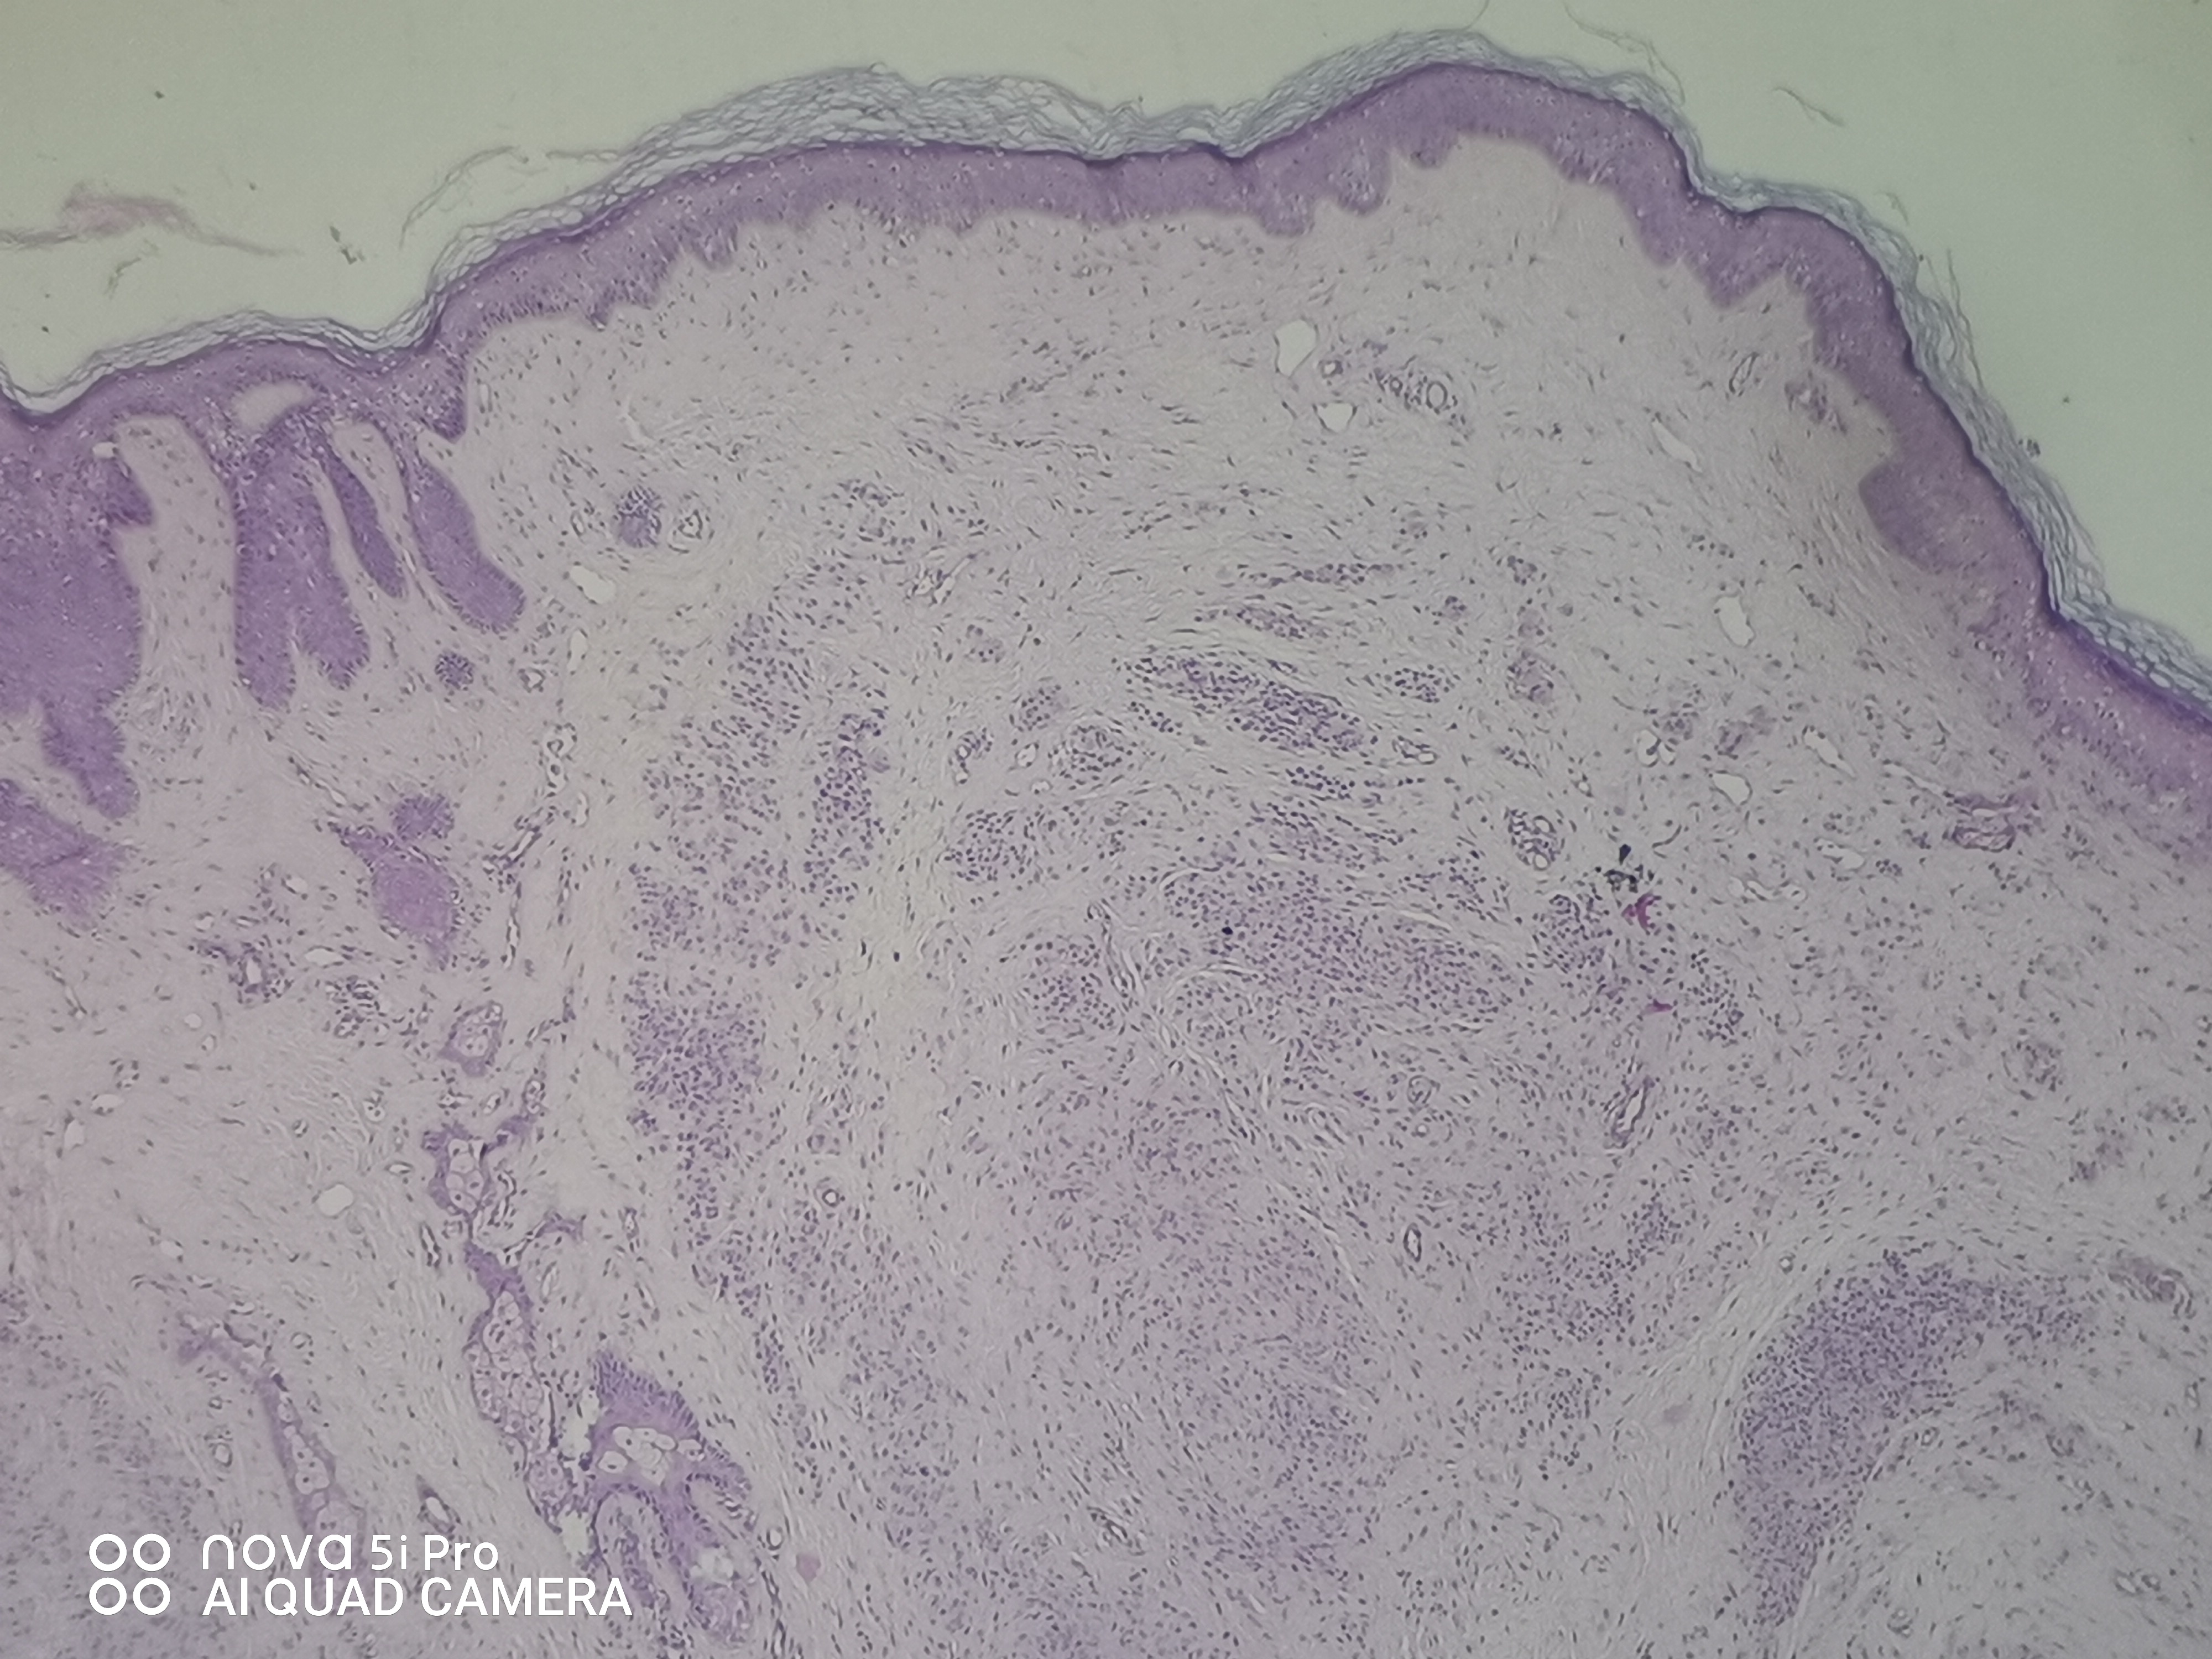

请老师们看看,右外耳道肿块,皮内痣?有问题吗?

性别

女

年龄

41岁

临床诊断

待查

一般病史

发现右外耳道肿块41年

标本名称

右外耳道肿块

大体所见

组织一块,大小约0.9*0.8*0.6cm,对半切开,灰白质中。全取

图1

皮内痣

皮内痣,报切缘